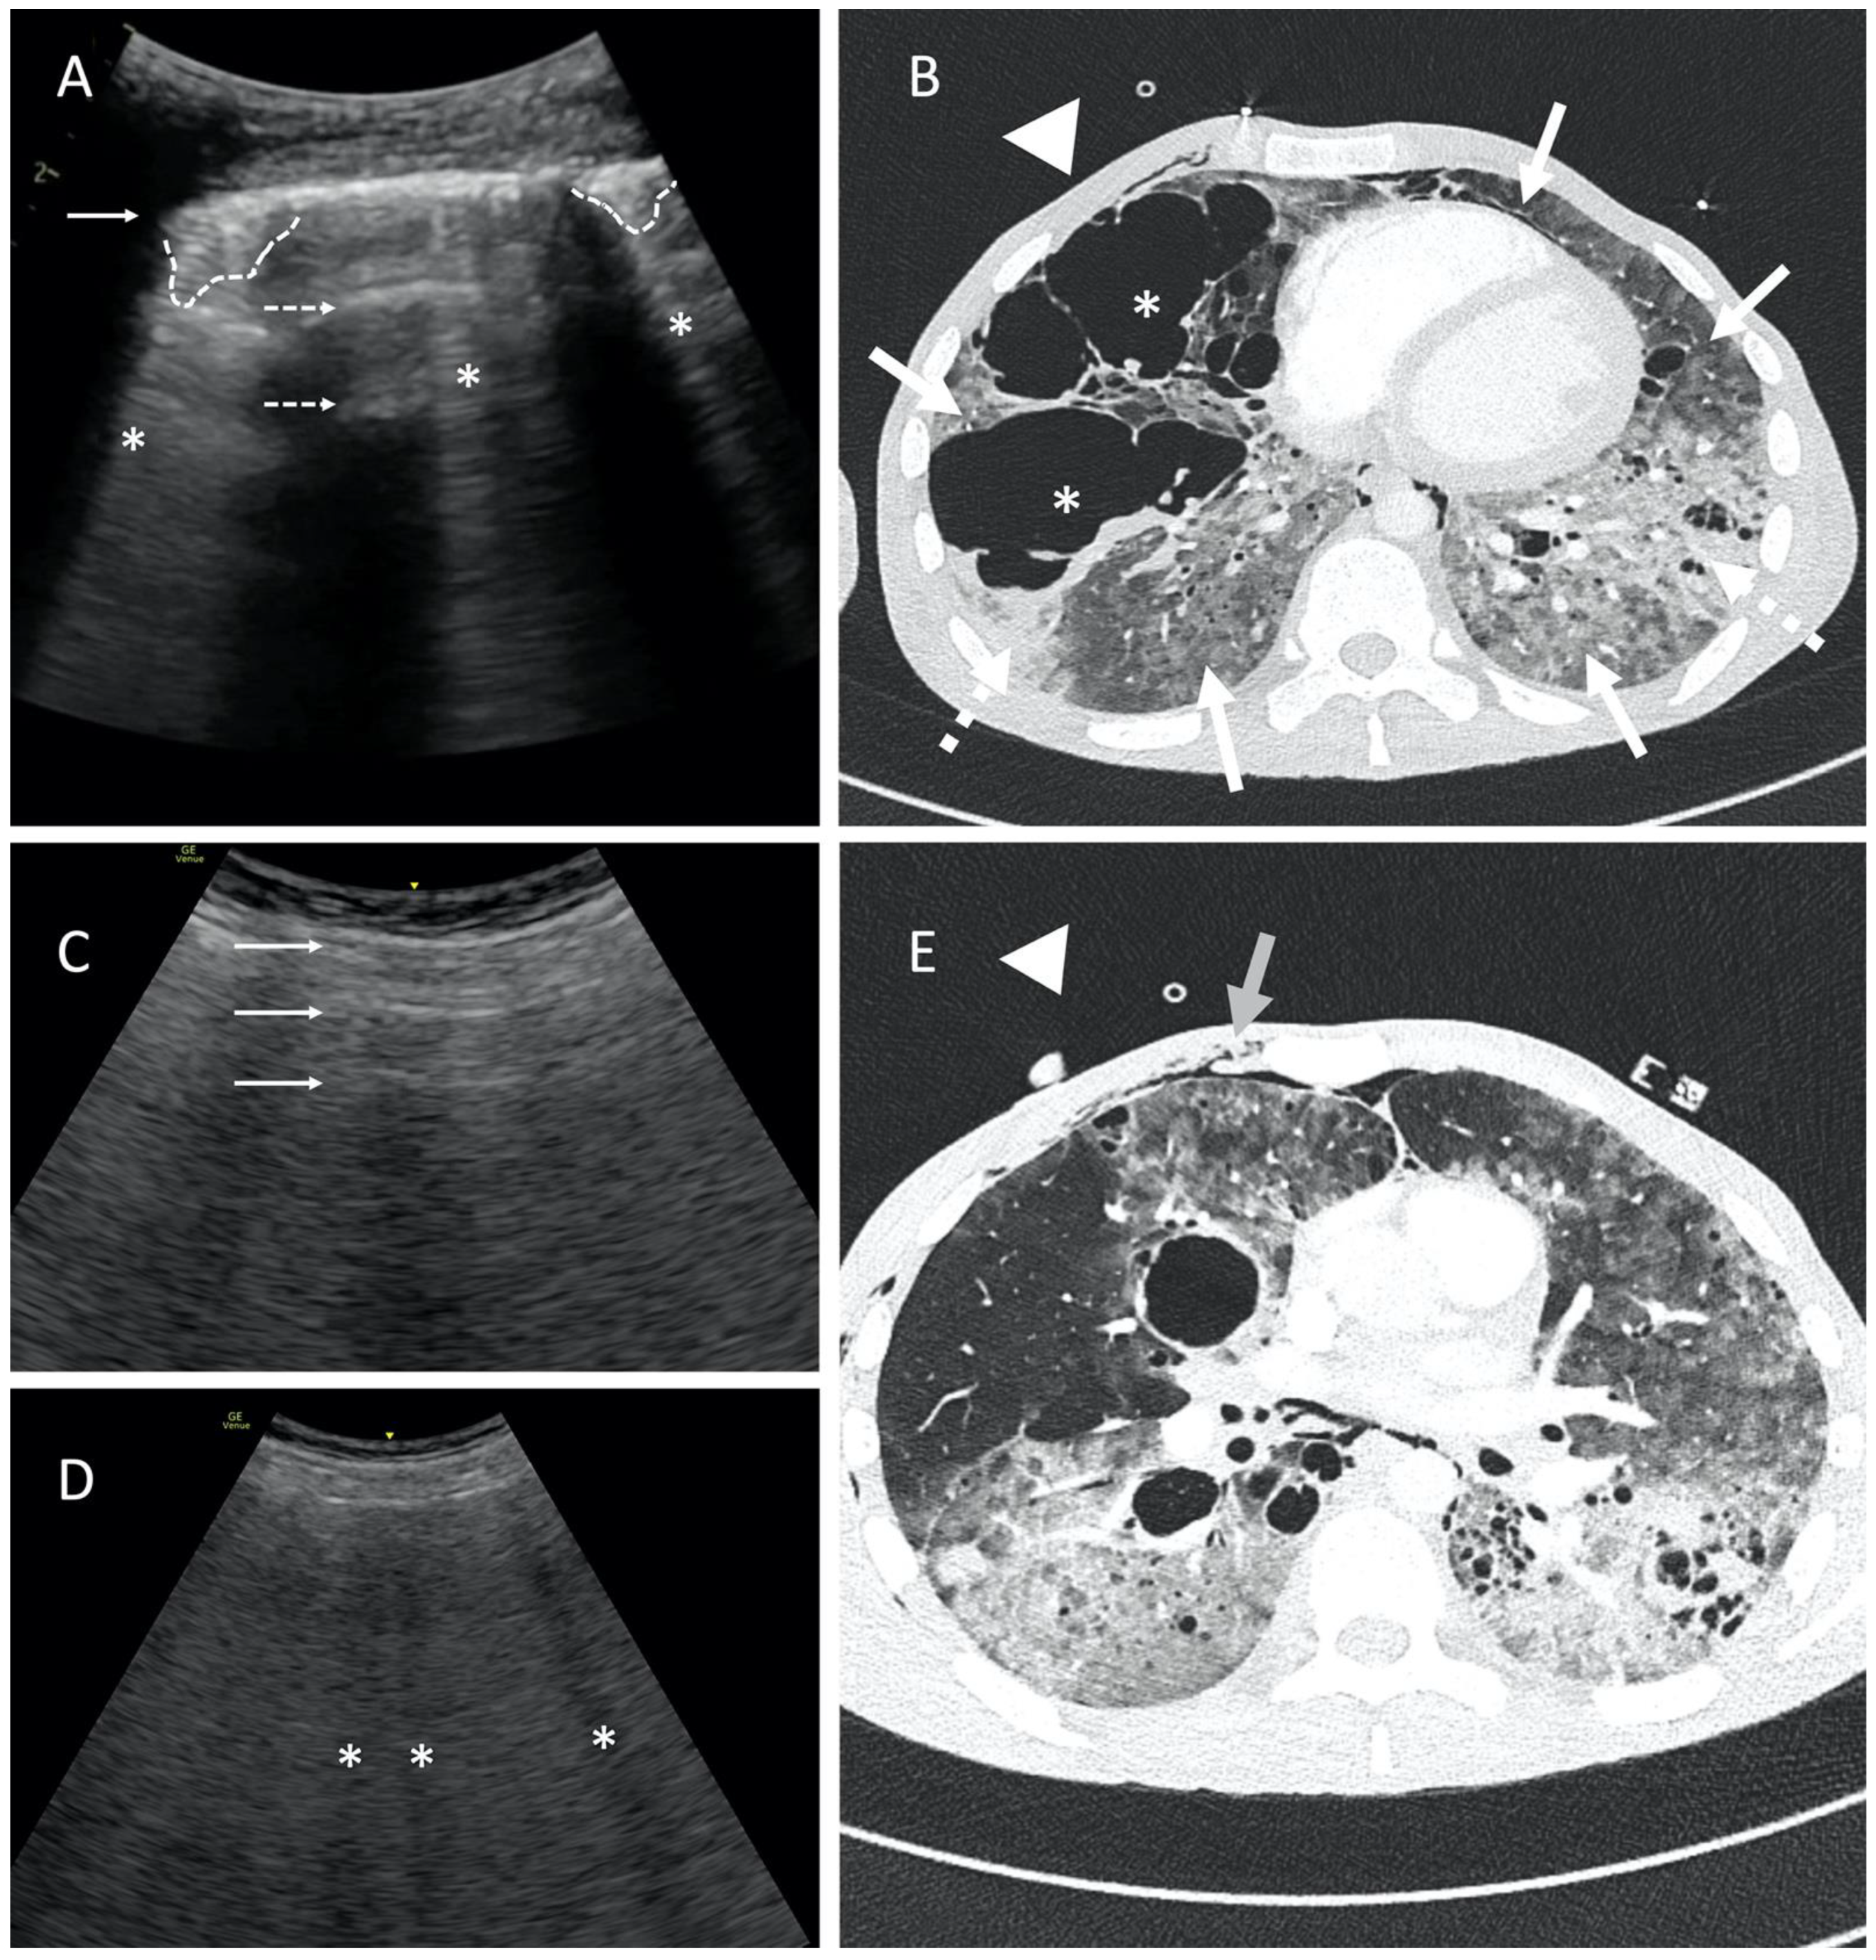

According to the literature, “the presence of subpleural artifacts rules out pneumothorax in 100%”. We would rather agree on 99%. Comet tails artifacts may result from the presence of pleural adhesions in the pneumothorax chamber or ruptured bullous emphysema, which imitate the physiological connective tissue septa (Figure 3A,B; Video S3A,B) [5]. Also, subcutaneous emphysema is particularly disruptive to a lung ultrasound as it may obscure both normal structures and mimic other pathologies. In the area of subcutaneous emphysema, LUS may completely lose diagnostic value and should be interpreted with extreme caution. The presence of air in the subcutaneous tissue can mimic the A-profile as well as B-profile and subpleural consolidations (Figure 3C–E). For this reason, it is crucial to position the probe transversely to the ribs and correctly identify the anatomical landmarks.

Figure 3.

Point-of-care LUS image of 24-year-old male with human immunodeficiency virus (HIV) infection, ARDS, and suspected atypical bacterial pneumonia. Patient was ventilated with guaranteed tidal volume (Bilevel Volume Guarantee; FiO2 100%; Vt 400 mL; PEEP 6 cmH2O; PIP 30 cmH2O). The study was performed using a 1.8–6 MHz convex probe. Presence of comet tail artifacts imitating B-lines carries a high risk of improper pneumothorax exclusion. (A) A-profile with blurred, fragmented pleural line (solid arrow), horizontal reverberations (dashed arrows), and disseminated subpleural consolidations (dashed lines). Note comet tail artifacts emerging most likely from subpleural structures (asterisks). Please refer also to Video S3. (B) CT image shows advanced bullous emphysema (asterisks), massive consolidations (dashed arrows), and diffused ground-glass opacification (solid arrows). The probe position is marked with a triangle. (C) LUS image of horizontal artifacts similar to A-line (solid arrows) and (D) hypoechoic vertical artifacts mimicking B-lines (asterisks) in some way, limiting the utility of ultrasound in pneumothorax detection. Note the ribs and rib shadows are not visible; the pleural line is not visible. (E) The LUS image corresponds to subcutaneous emphysema in the upper part of the chest wall in CT scan (solid arrow). The probe position is marked with a triangle.